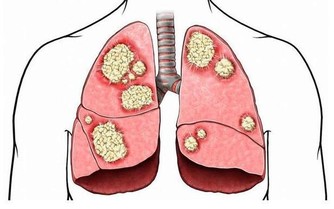

甚至導致皮膚發生各種病變:長痤瘡(青春痘)、長雀斑、長瘢痕等,在肌肉則形成腫瘤,痰核,在血管則形成浮絡,靜脈曲張,靜脈瘤等現象,而這些代謝又有可能形成另一個病症,如失眠、頭痛、鼻病等,如此因果循環則皮膚的代謝功能必定降低,從而加快了皮膚衰退老化的速度。